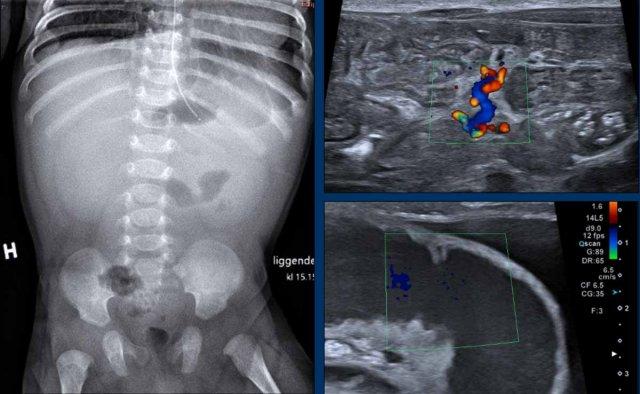

Hình ảnh

Bé trai 4 tháng tuổi đã phẫu thuật tim bẩm sinh phức tạp, hiện có phân lẫn máu.

X-quang bụng cho thấy khí trong thành ruột (pneumatosis) (mũi tên).

Dấu hiệu này cũng được thấy trên siêu âm ở đoạn ruột bên trái, trong khi đoạn ruột lành bên phải cho thấy các phản âm hơi bình thường.

X-quang của trẻ 2 tháng tuổi có nôn mật sau phẫu thuật thoát vị hoành. Có rất ít hơi trong ruột phù hợp với tình trạng nôn và ruột xẹp. Trên siêu âm thấy cổ trướng và một quai ruột giãn với giảm tưới máu. Trong mạc treo thấy hình ảnh xoắn vặn của các mạch máu phù hợp với xoắn ruột.

Tiếp tục xem video của bệnh nhân này….